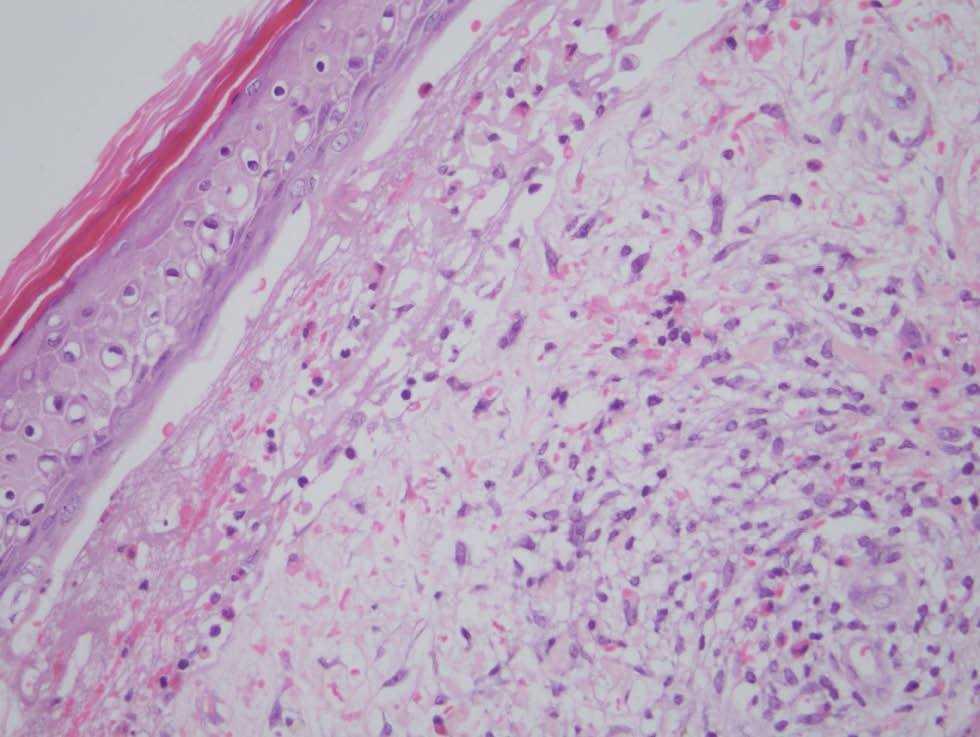

En la analítica destacaba la presencia de 36.800 leucocitos/mm 3 con 81 % de linfocitos; la bioquímica y la coagulación eran normales. Se realizó una biopsia cutánea de una ampolla (fig. 3) y de una pápula edematosa (fig. 4).

Fig. 4.--En dermis observamos una reacción inflamatoria perivascular e intersticial de células mononucleadas con abundantes eosinófilos.(Hematoxilina-eosina, x40.)

En la biopsia de la lesión ampollosa se aprecia una ampolla subepidérmica, cuyo techo está constituido por un epitelio parcialmente necrótico con reepitelización y el suelo por las papilas dérmicas. La ampolla contiene fibrina, células mononucleadas y múltiples eosinófilos (fig. 3). En la pápula edematosa existe en la epidermis un intenso edema inter e intracelular, que induce la formación de vesículas basales y ruptura de la membrana basal. En ambas biopsias vemos en toda la dermis reacción inflamatoria perivascular e intersticial de células mononucleadas con abundantes eosinófilos, intensa ectasia capilar y edema (fig. 4). La inmunofluorescencia directa sobre piel perilesional de una ampolla fue negativa.